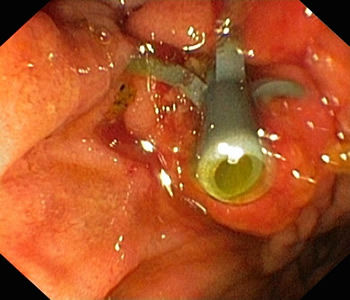

术中医护人员克服了患者体位不正、无X线协助等困难,成功为其进行十二指肠乳头插管,术中见大量脓性胆汁喷出,并取出较多泥沙样结石,置入内引流支架,不到30分钟快速完成手术。

床旁开展ERCP 超声协助定位

喷出脓性胆汁 留置胆管支架